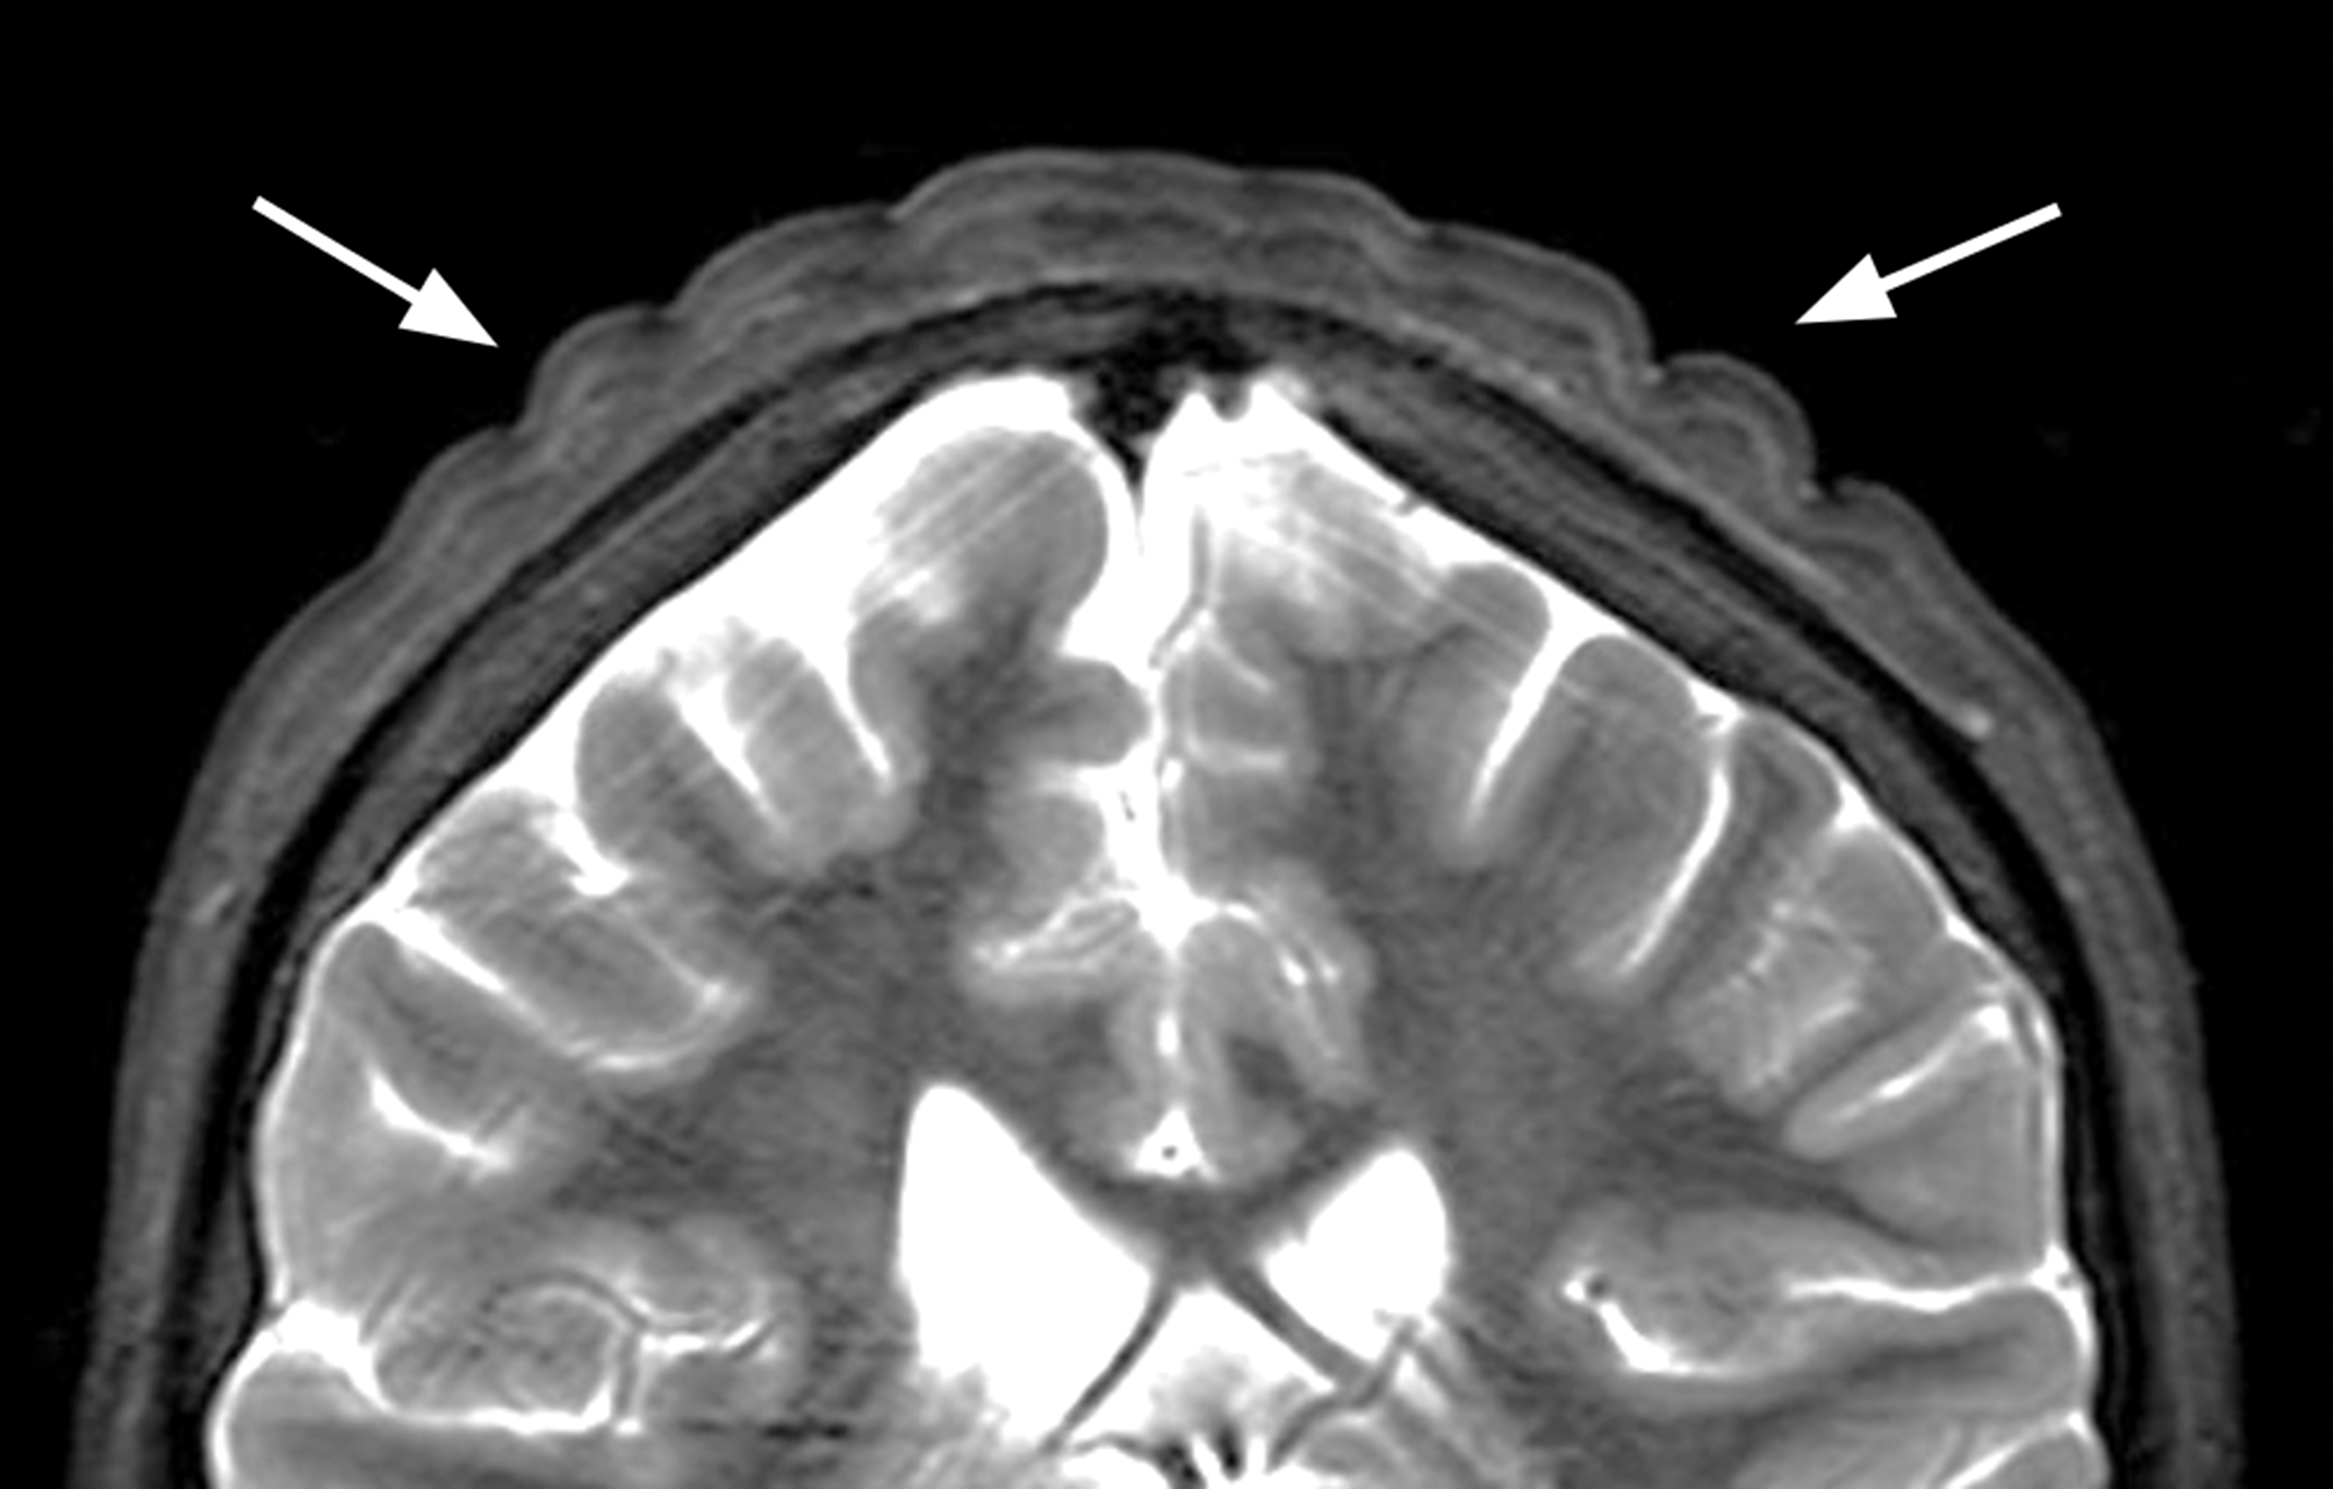

Figure 2

Coronal T2‑weighted image showing the thickened skin folds.

A 13‑year‑old boy with known Prader–Willi syndrome treated with growth hormone therapy (somatropin), since the age of 6 years, was presented to the outpatient pediatric endocrinology clinic with a groove‑shaped swelling of the scalp with anteroposterior orientation in the past 4 weeks (Figure 1). Brain MRI showed bilateral parietal groove‑shaped thickening of the cutis and subcutis in an anteroposterior orientation giving the scalp a ‘cerebral cortex like appearance’ (Figure 2). No intracranial abnormalities were seen. The imaging characteristics were fairly typical for cutis verticis gyrata (CVG).